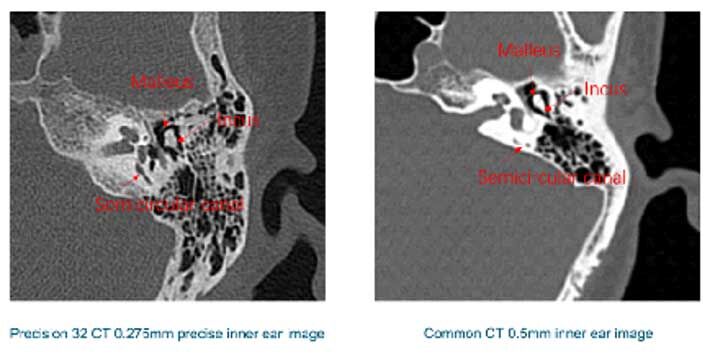

High quality images are closely related to advanced CT reconstruction algorithm, we independently develop the Hi-Resolution HD algorithm, combine with 1024x1024m image matrix, the human body and lesion structure could be displayed to the extreme.

The conventional thin-slice CT image shows a GGN in the right lung. The image reconstructed by high resolution algorithm of YSCT-128C shows the internal structure of the nodule which is composed of microvessels and nodule actually.